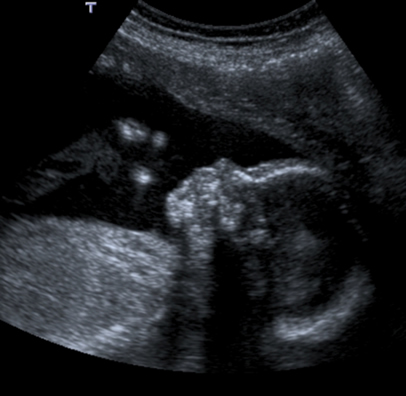

In the normal fetus at about 20 weeks, the frontal bone and facial bones are clearly seen.

The anencephalic fetus demonstrates no clear frontal bone and often the facial bones may appear unusual also with the orbits appearing prominent – the so called 'frog-eyed appearance'. There may be some brain visible but this is variable. There is no bright skull vault covering the brain.

This image shows the facial view of an anencephalic fetus. Note the frog-eyed appearance. Also note that the skull vault is completely absent.